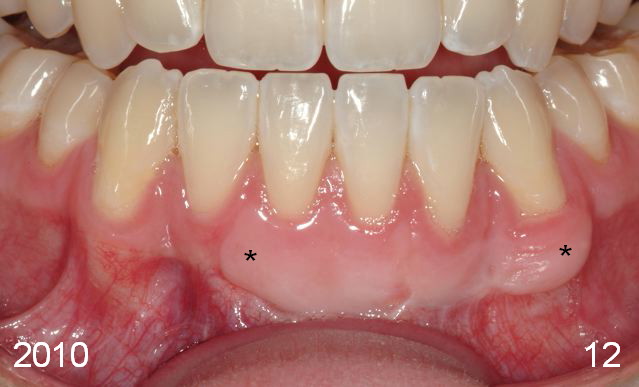

Initial information was obtained on 02/26/2014 (Fig.1-10). Anterior edge-to-edge and Posterior Open Bite (Fig.4 *): unfavorable differential Class III growth after orthodontics as a child.

The labial gingival recession of the lower anterior teeth (Fig.11) was treated with gingival graft (Fig.5,12*). One of the last things Chip Webster did before he died! God rest his soul.